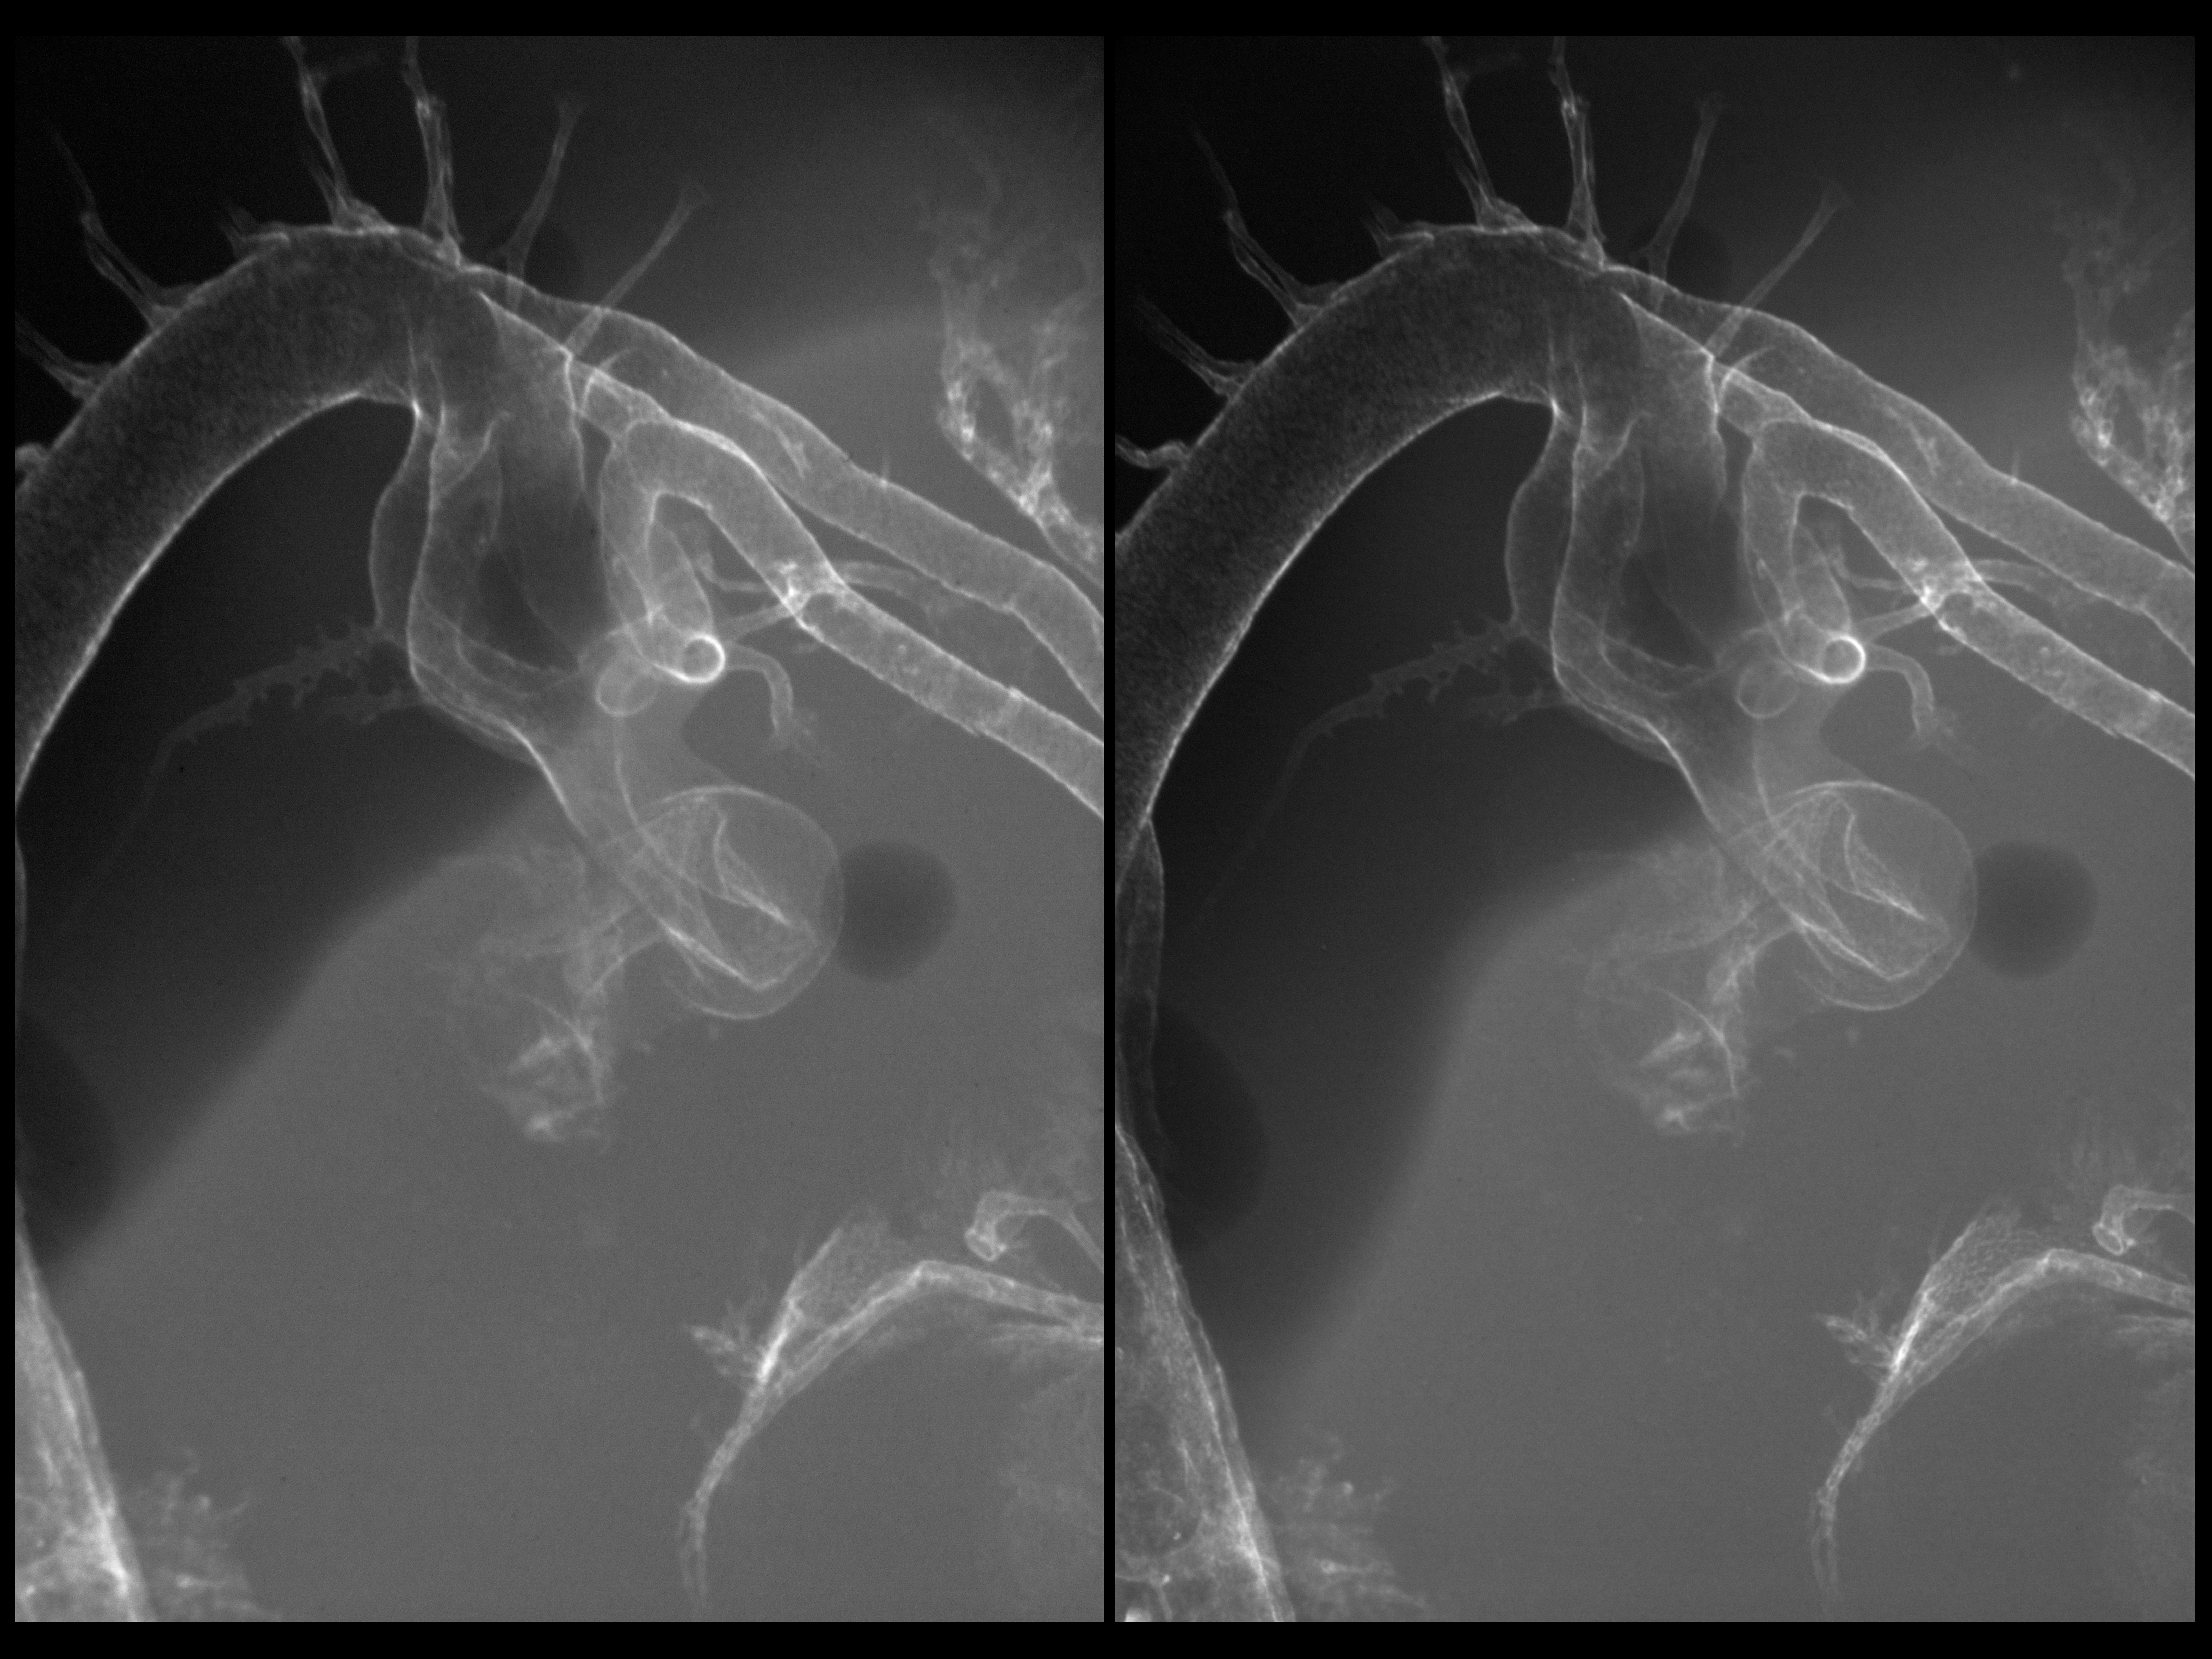

Stereo X-Ray Micrographs